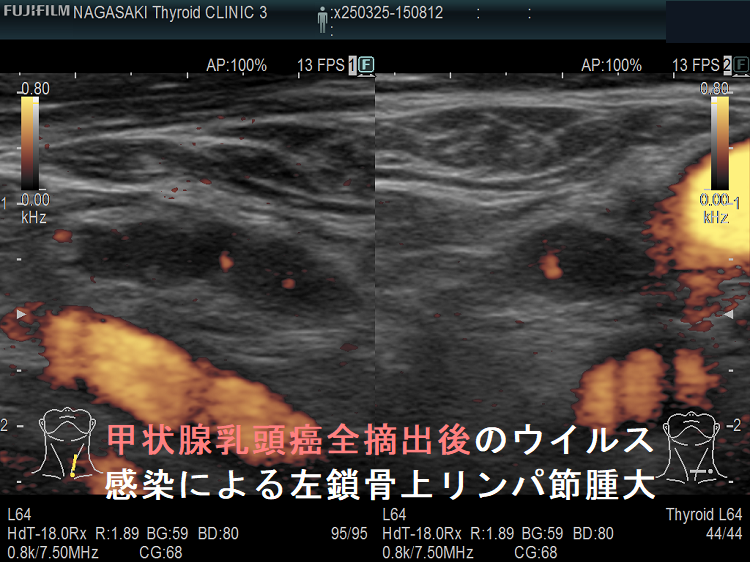

甲状腺乳頭癌全摘出後のウイルス感染による左鎖骨上リンパ節腫大

甲状腺乳頭癌全摘出後のウイルス感染による左鎖骨上リンパ節腫大;非常に紛らわしいが、明らかな圧痛も伴う。数か月で縮小。

甲状腺乳頭癌全摘出後のウイルス感染による左鎖骨上リンパ節腫大(拡大) ドプラーモード

甲状腺乳頭癌全摘出後のウイルス感染による左鎖骨上リンパ節腫大(拡大) ドプラーモード;内部血流も正常